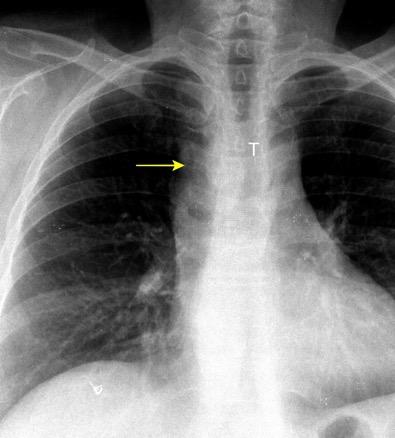

30 años

Borramiento de la banda PARA-aórtica por AdenoCa. de LII, no visible en 2005

Colapso de LII. TC: secreciones bronquiales.

Endoscopia tapón mucopurulento extraído

Borramiento parcial por Ca. epidermoide.